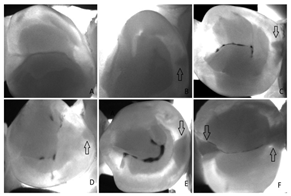

4.3.4. Near-Infrared Transillumination

Near-infrared transillumination (TI) is a promising and effective imaging technique for the detection of early teeth lesions (i.e., caries) in real-time without film [41,81]. Increased mineral loss (caries lesion) leads to an increase in scattering and absorption of light. Therefore, caries appears as dark regions because less light reaches the detector [81].

| Near-Infrared Transillumination | [10,41] | Early teeth lesions (i.e., caries) in real time | ![]() | The near-infrared light shows as a dark region in a caries lesion because of light scattering and absorption. |